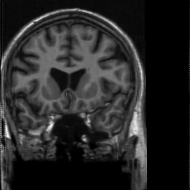

4.3 Medical Image Compressive Sensing

Medical image compressive sensing is an everlasting practical application in image reconstruction area. In this section we test the performance of the proposed ResGD-Net on compressive sensing reconstruction of brain MR images [3] (CS-MRI). In CS-MRI problem, the data fidelity term is , where , is a binary selection matrix representating the sampling trajectory, and is the discrete Fourier transform. We randomly pick images from the brain MRI datasets [3], then crop and keep the central part with less background. Then we at random divide the dataset to images for training and for testing. Among this section, we present the comparison results between ResGD-Net and ISTA-Net+ [33], where the latter one is a state-of-the-art method in tackling with CS-MRI problem. For fairness, both algorithms compared here are evaluated on the same dataset and metrics. Experiments are conducted across different sampling ratios , and of to show the generality. The study of ResGD-Net on different sampling ratios and various phase numbers is shown in Fig. 4. The PSNR comparison with ISTA-Net+ is shown in Table. 2. The result enhancement of the proposed ResGD-Net against ISTA-Net+ is remarkable across all sampling ratios even though we only use approximately many number of parameters than ISTA-Net+ [33].

In addition, we provide the visualization results of some selected MR images reconstructed by the state-of-the-art ISTA-Net+ [33] and our proposed ResGD-Net on compressive sensing (CS) ratio , and . The results are evaluated under metrics the Peak Signal-to-Noise Ratio (PSNR), the Structural Similarity (SSIM) and the Mean Squared Error (MSE). For better visualization, we rescale the pixel value by multiplying on the error maps (the second row of Figs. 5 - 7) when displaying.

PSNR: dB

SSIM:

MSE:

PSNR: dB

SSIM:

MSE:

PSNR: dB

SSIM:

MSE:

PSNR: dB

SSIM:

MSE:

PSNR: dB

SSIM:

MSE:

PSNR: dB

SSIM:

MSE: